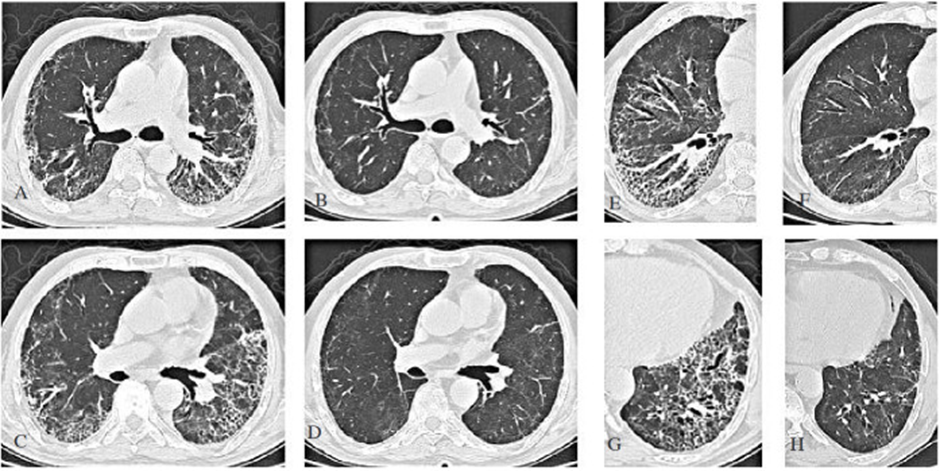

a-c-e-g: CT ngực của bệnh nhân có biểu hiện khó thở ở tuần 13 sau nhiễm COVID-19. b-d-f-h: Sự thoái lui đáng kể các tổn thương tuần thứ 25 sau khi điều trị bằng steroid. (From archives of Aydın Yılmaz)